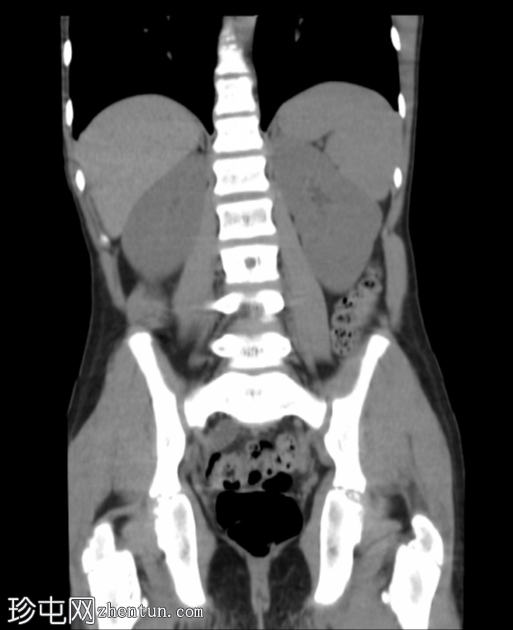

冠状位

平扫

冠状位重建

显示输尿管显影

腹部和盆腔CT扫描结果正常。

泌尿系统正常。未见尿路结石或反流压改变。

本病例显示一名10岁男孩的腹部、盆腔和泌尿系统CT扫描结果正常。